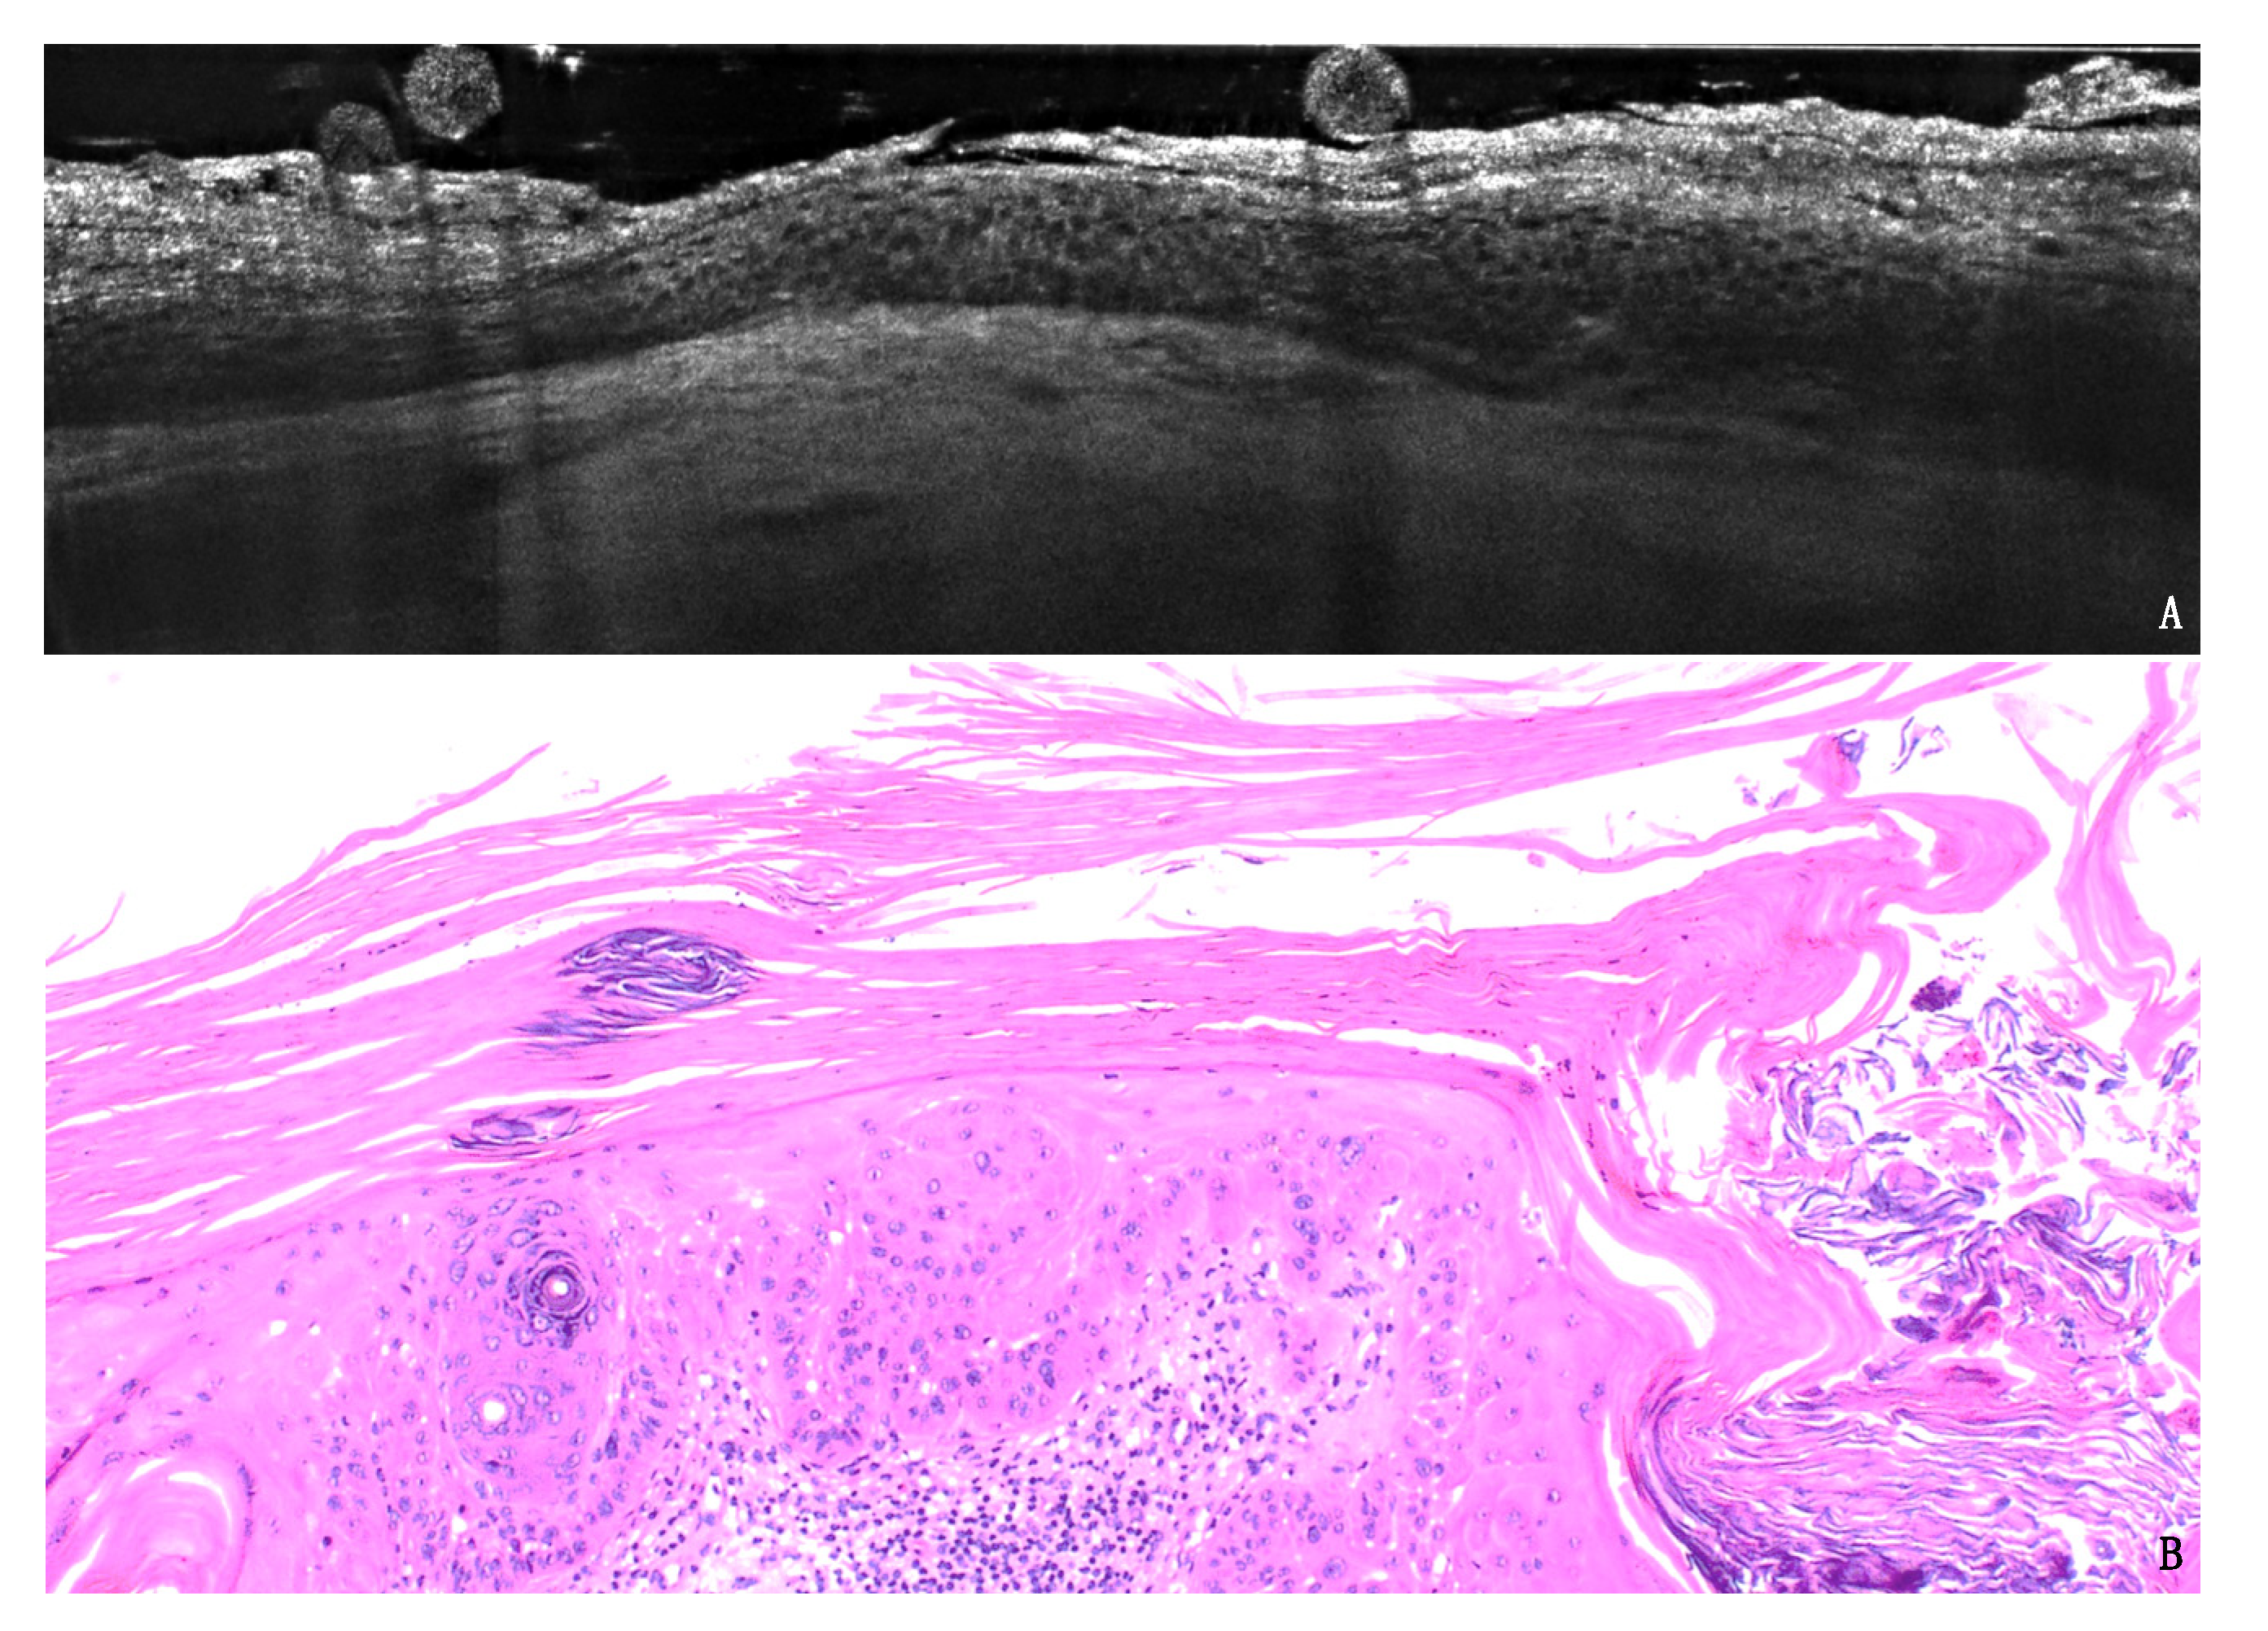

In-Vivo LC-OCT Evaluation of the Downward Proliferation Pattern of Keratinocytes in Actinic Keratosis in Comparison with Histology: First Impressions from a Pilot Study

3. Results

3.1. PRO Grading